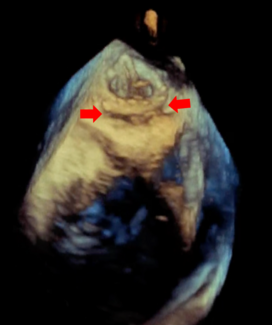

Over 5.7 million people in US and 20 million people worldwide suffer from heart failure and about half of these suffer from Heart Failure with Preserved Ejection Fraction (HFpEF). Most drug trials have shown minimal beneficial effects, and attention has turned to possible device therapy. The CORolla is an elastic device implanted in the LV through transapical approach or percutaneous approach. The device applies direct internal expansion forces distributed on the LV wall and the septum. Clinical studies are in progress. The ImCardia device is an elastic expanding device that is attached to external LV surface through off pump procedure. A study in patients admitted for AVR secondary to aortic stenosis showed trends to improvement in diastolic dysfunction after 24 months.